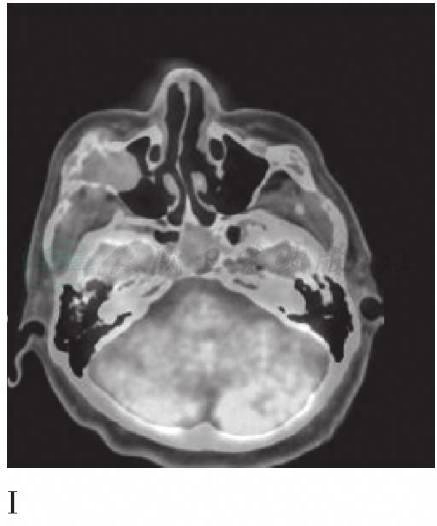

A. CT颅骨三维重建图;B. FDG PET脑3D图像;C. 18FECH PET脑3D图像;D. 18FECH PET图显示鞍区占位高代谢;E. CT鞍区图像;F. 18FECH PET/CT显示鞍区占位高代谢灶;G. FDG PET显示鞍区占位高代谢;H. CT鞍区图像;I. FDG PET/CT显示鞍区占位高代谢灶;J. FDG PET 3D显示锁骨等多处高代谢灶;K. 18FECH PET 3D显示双侧锁骨等多处高代谢灶

18FECH PET/CT提示颅骨多发骨质破坏,病变区SUVmax为5.7,与大脑皮层的SUVmax比值为14.3;右侧上颌窦和鞍区软组织密度影的SUVmax为5.1~5.8(图1D、E、F),与大脑皮层的SUVmax比值为12.8~14.5;左侧的胸锁关节和双侧肩关节骨质破坏,病灶的SUVmax为4.0。FDG PET/ CT提示颅骨多发骨质破坏,病变区SUVmax为2.8,与大脑皮层的SUVmax比值为0.4;右侧上颌窦和鞍区可见软组织密度影(图1G、H、I),病灶SUVmax为4.3~6.0,与大脑皮层SUVmax比值为0.7~0.9;左侧胸锁关节和双侧肩关节骨质破坏,病灶的SUVmax为2.2。